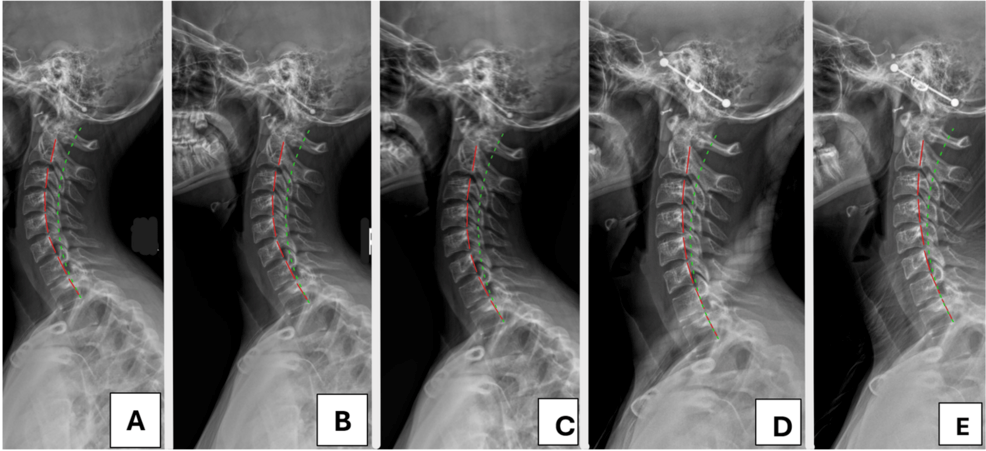

İleri Cerrahi Teknikler

Cerrahi yalnızca konservatif tedavilerin başarısız kaldığı durumlarda düşünülebilir. Prosedürler altta yatan nedene ve rahatsızlığın yaygınlığına bağlı olarak değişiklik gösterebilir.

• Mikrocerrahi: Bu minimal invaziv teknik, servikal omurgadaki hasarlı diskleri veya dokuları çıkarmak veya tedavi etmek için küçük kesiler ve özel aletler içeren küçük cerrahi işlemler

• Minimal İnvaziv Omurga Cerrahisi (MISS): MISS teknikleri, daha küçük kesilerle omurganın düzgün hizalanmasını sağlayarak, iyileşme sürelerini kısaltır ve riskleri en aza indirir.

• Spinal Füzyon: Ciddi servikal hizalama bozukluğu olan vakalarda, iki veya daha fazla omurun kemik greftleri kullanılarak birleştirilmesi ve böylece omurlar arasındaki hareketin ortadan kaldırılmasını içerir.